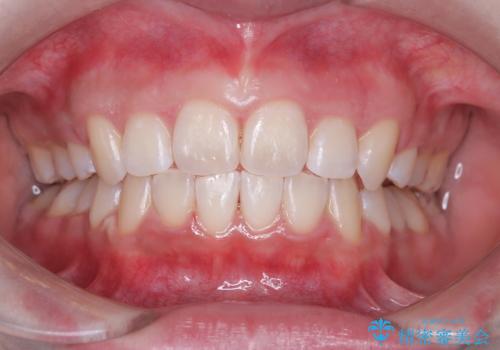

矯正後のホワイトニング希望

- 矯正治療が終わり歯並びも綺麗になったので黄色い歯を白くしたくなったようです。

歯並びや歯が綺麗になり笑顔も更に素敵に患者さまも喜んでいられました。

オフィスホワイトニングのブースト使用